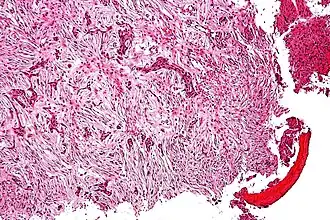

Microfotografia de um adamantinoma.

Adamantinoma ósseo é um tumor maligno de baixo grau, descrito por Fischer em 1913, acometendo pessoas da segunda e terceira décadas de vida, estando em 85% dos casos presente na tíbia. Cursa com metástase pulmonar de aparecimento tardio, da ordem de 15%.[1]

A clínica é de dor insidiosa e massa palpável, porém 20% abrem com quadro de fratura patológica. Diferencia-se da displasia osteofibrosa por esta incidir em menores de 10 anos, ser indolor e totalmente intracortical. Na radiologia, o adamantinoma apresenta-se como múltiplas lesões líticas excêntricas acometendo grande área em diáfise da tíbia com contornos bem definidos. Inicia-se na cortical, mas invade medular. Pode ainda invadir a fíbula por contiguidade.